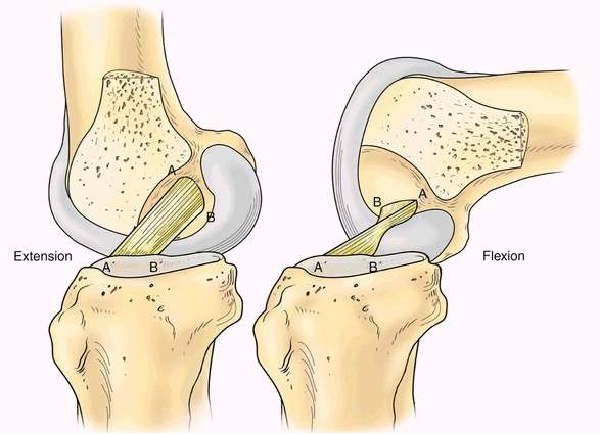

前交叉韧带双股重建

解剖基础

伸直时AM,PL的股骨点垂直排列,两束平行。

屈曲90°时,AM,PL的股骨点平行,两束交叉

膝关节屈曲90 °时PL松弛,而伸直时PL紧张状态

理论基础

双束重建能更好的解剖重建交叉韧带,使得重建的交叉韧带更加符合生物力学。